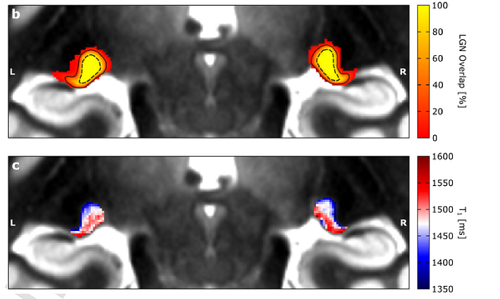

Hochauflösende MRT macht bisher verborgene Gebiete des menschlichen Gehirns sichtbar19. Oktober 2021 Foto: © Christa Müller-Axt Ein Team von Neurowissenschaftlern an der Technischen Universität Dresden hat eine neuartige, nichtinvasive bildgebungsbasierte Methode zur Untersuchung des visuell-sensorischen Thalamus entdeckt. Diese könnte in naher Zukunft ein vertieftes Verständnis der visuellen Sinnesverarbeitung ermöglichen. Der visuell-sensorische Thalamus ist eine wichtige Struktur des menschlichen Gehirns, die aus zwei Teilen besteht. Die Symptome vieler Krankheiten wie Legasthenie und Grüner Star werden mit Veränderungen in dieser Region in Verbindung gebracht. Bisher war es sehr schwierig, diese beiden Teile am lebenden Menschen zu untersuchen, da sie winzig sind und sich sehr tief im Inneren des Gehirns befinden. Diese Schwierigkeit, den visuell-sensorischen Thalamus im Detail zu untersuchen, hat das Verständnis über die Funktionsweise der visuellen Sinnesverarbeitung in der Vergangenheit stark beeinträchtigt. Christa-Müller Axt ist Doktorandin und beschäftigt sich in der Abteilung von Neurowissenschaftlerin Prof. Katharina von Kriegstein an der TU Dresden mit dem visuell-sensorischen Thalamus. Durch Zufall entdeckte die Doktorandin in Neuroimaging-Daten Strukturen, die den beiden visuell-sensorischen Thalamusteilen ähnelten. Die Neuroimaging-Daten waren einzigartig, da sie eine äußerst hohe räumliche Auflösung aufwiesen und mit einem speziellen Magnetresonanztomographen (MRT) am MPI-CBS in Leipzig aufgenommen wurden, wo von Kriegsteins Gruppe neurowissenschaftliche Studien zu Legasthenie durchführte. Müller-Axt verfolgte diese Entdeckung in einer Reihe weiterer Experimente, bei denen sie In-vivo- und Post-mortem-MRT-Daten mit hoher räumlicher Auflösung sowie post-mortem-Histologie analysierte. Die Ergebnisse zeigen, dass die zwei Teile des visuell-sensorischen Thalamus durch unterschiedliche Mengen an Myelin gekennzeichnet sind. Diese Information lässt sich in den neuartigen MRT-Daten erkennen und kann somit zur detaillierten Untersuchung des visuell-sensorischen Thalamus beim lebenden Menschen verwendet werden. Das obere Feld zeigt die Lage des visuell-sensorischen Thalamus in den hochauflösenden MRT-Daten. Je gelber die Farbe, desto mehr Teilnehmende haben den visuell-sensorischen Thalamus an dieser Stelle. Das untere Feld zeigt, dass Informationen über die Menge der weißen Substanz verwendet werden können, um die beiden Teile des visuellen Thalamus zu unterscheiden. (Abb.:© CC BY-NC) “Die Erkenntnis, dass wir die Teile des visuell-sensorischen Thalamus bei lebenden Menschen darstellen können, ist fantastisch. In naher Zukunft kann man damit die visuell-sensorische Verarbeitung sowohl bei gesunden, als auch bei kranken Menschen untersuchen”, sagt Müller-Axt und erklärt: “Post-mortem-Studien bei Legasthenie haben gezeigt, dass es speziell in einem der beiden Teile des visuell-sensorischen Thalamus strukturelle Veränderungen gibt. Jedoch gibt es nur sehr wenige dieser Post-mortem-Untersuchungen, weswegen es schwierig ist zu sagen, ob alle Legastheniker diese Art von Veränderungen im visuell-sensorischen Thalamus aufweisen. Außerdem können Post-mortem-Daten nichts über die funktionellen Auswirkungen dieser Veränderungen und ihren spezifischen Beitrag zu den Entwicklungssymptomen der Legasthenie aussagen. Daher erwarten wir, dass unser neuartiger In-vivo-Ansatz die Forschung über die Rolle des visuell-sensorischen Thalamus bei Legasthenie erheblich erleichtern und vorantreiben wird.” Originalpublikation: Müller-Axt C et al. Mapping the human lateral geniculate nucleus and its cytoarchitectonic subdivisions using quantitative MRI. NeuroImage 2021;244:118559.